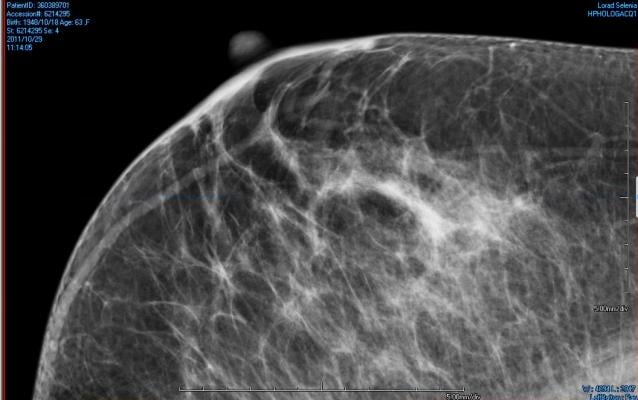

March 9, 2016 — The use of diabetes treatment, whether by diet or pills such as metformin, decreases mammographic density (MD), one of the strongest risk factors for breast cancer, whereas taking insulin appears to increase it. These findings were part of a presentation at the 10th European Breast Cancer Conference.

The group had a mean (average) age of 56 years; 137 (2.4 percent) had diabetes and 3,180 (56.3 percent) had breasts categorized as mixed or dense breasts. "Women with diabetes were less likely to have mixed or dense breasts, as opposed to fatty ones, both before and after adjustment for other factors such as being overweight," Andersen said.

Similar inverse associations were found in the 44 women who controlled diabetes by diet alone, and the 62 who took oral medication for the condition. However, diabetic women using insulin injections had increased odds of having mixed or dense breasts. These associations were not modified by menopausal status or by body mass index (BMI).

Breast density is one of the strongest risk factors for breast cancer, with women with high density breasts (more than 75 percent density) having a four to six times greater risk than women with an MD of less than 25 percent. However, the researchers emphasize that the finding that insulin treatment is associated with increased MD does not imply that it increases breast cancer risk. "Breast density is only one of many risk factors for developing breast cancer," said Andersen. "Denmark is fortunate to have such a large MD data set, which, through the DCH study group, can be linked to many different issues that may influence health outcomes. The possibility of analyzing such detailed information in a coherent group means that we have the ability to undertake additional studies in order to further investigate the relationships between breast density and other risk factors for breast cancer.